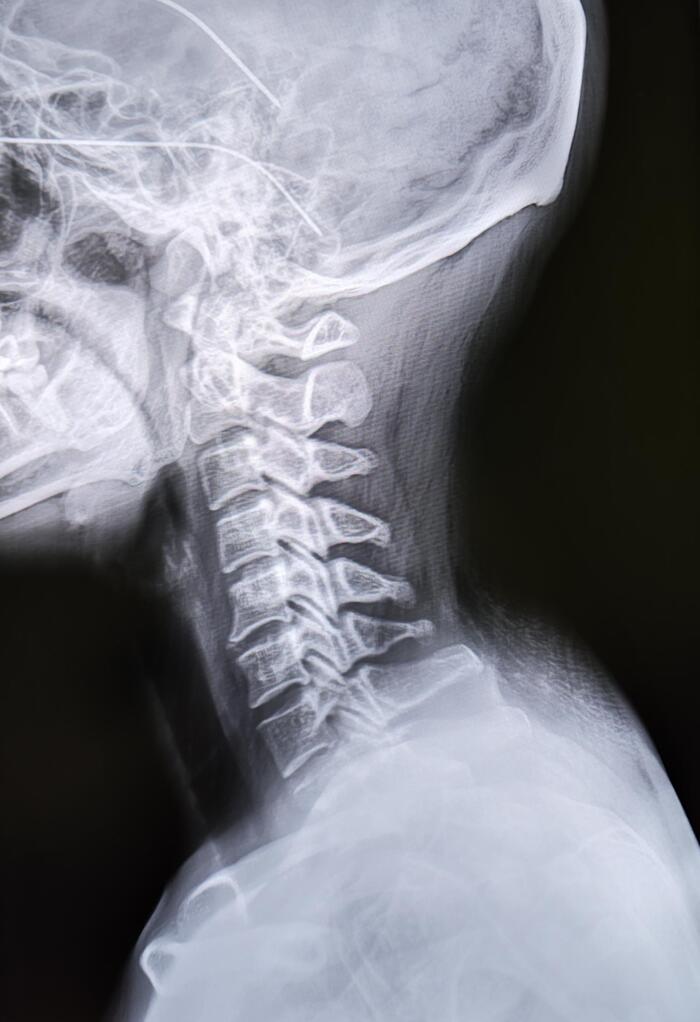

Пациентка (34года) пришла на Р-гр. ШОП, с жалобами на возникшее образование по задней поверхности шеи.

Вдовий горб – локальное скопление жировой ткани на границе шеи и спины при котором образуется характерная выпуклость.

Причины возникновения: недостаточная физическая активность, постоянное нахождение в позе, при которой голова согнута, эндокринные нарушения, мышечные дистрофии, менопауза(изменение гормонального фона).